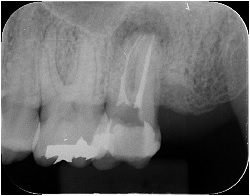

1番右の歯が腫れている歯のレントゲン像になります。

上の歯なので、画像の下の方が歯の頭で、画像の上の方が歯の根っこになります。

他の歯との違いがあるのですが、分かるでしょうか。

他の歯と違って、根の先が黒っぽくなっているのが分かります。

これは主に根の中の細菌の影響で、骨を一部溶かしてしまっている状態なのです。

骨が溶けた分、根の先が黒っぽく見えています。